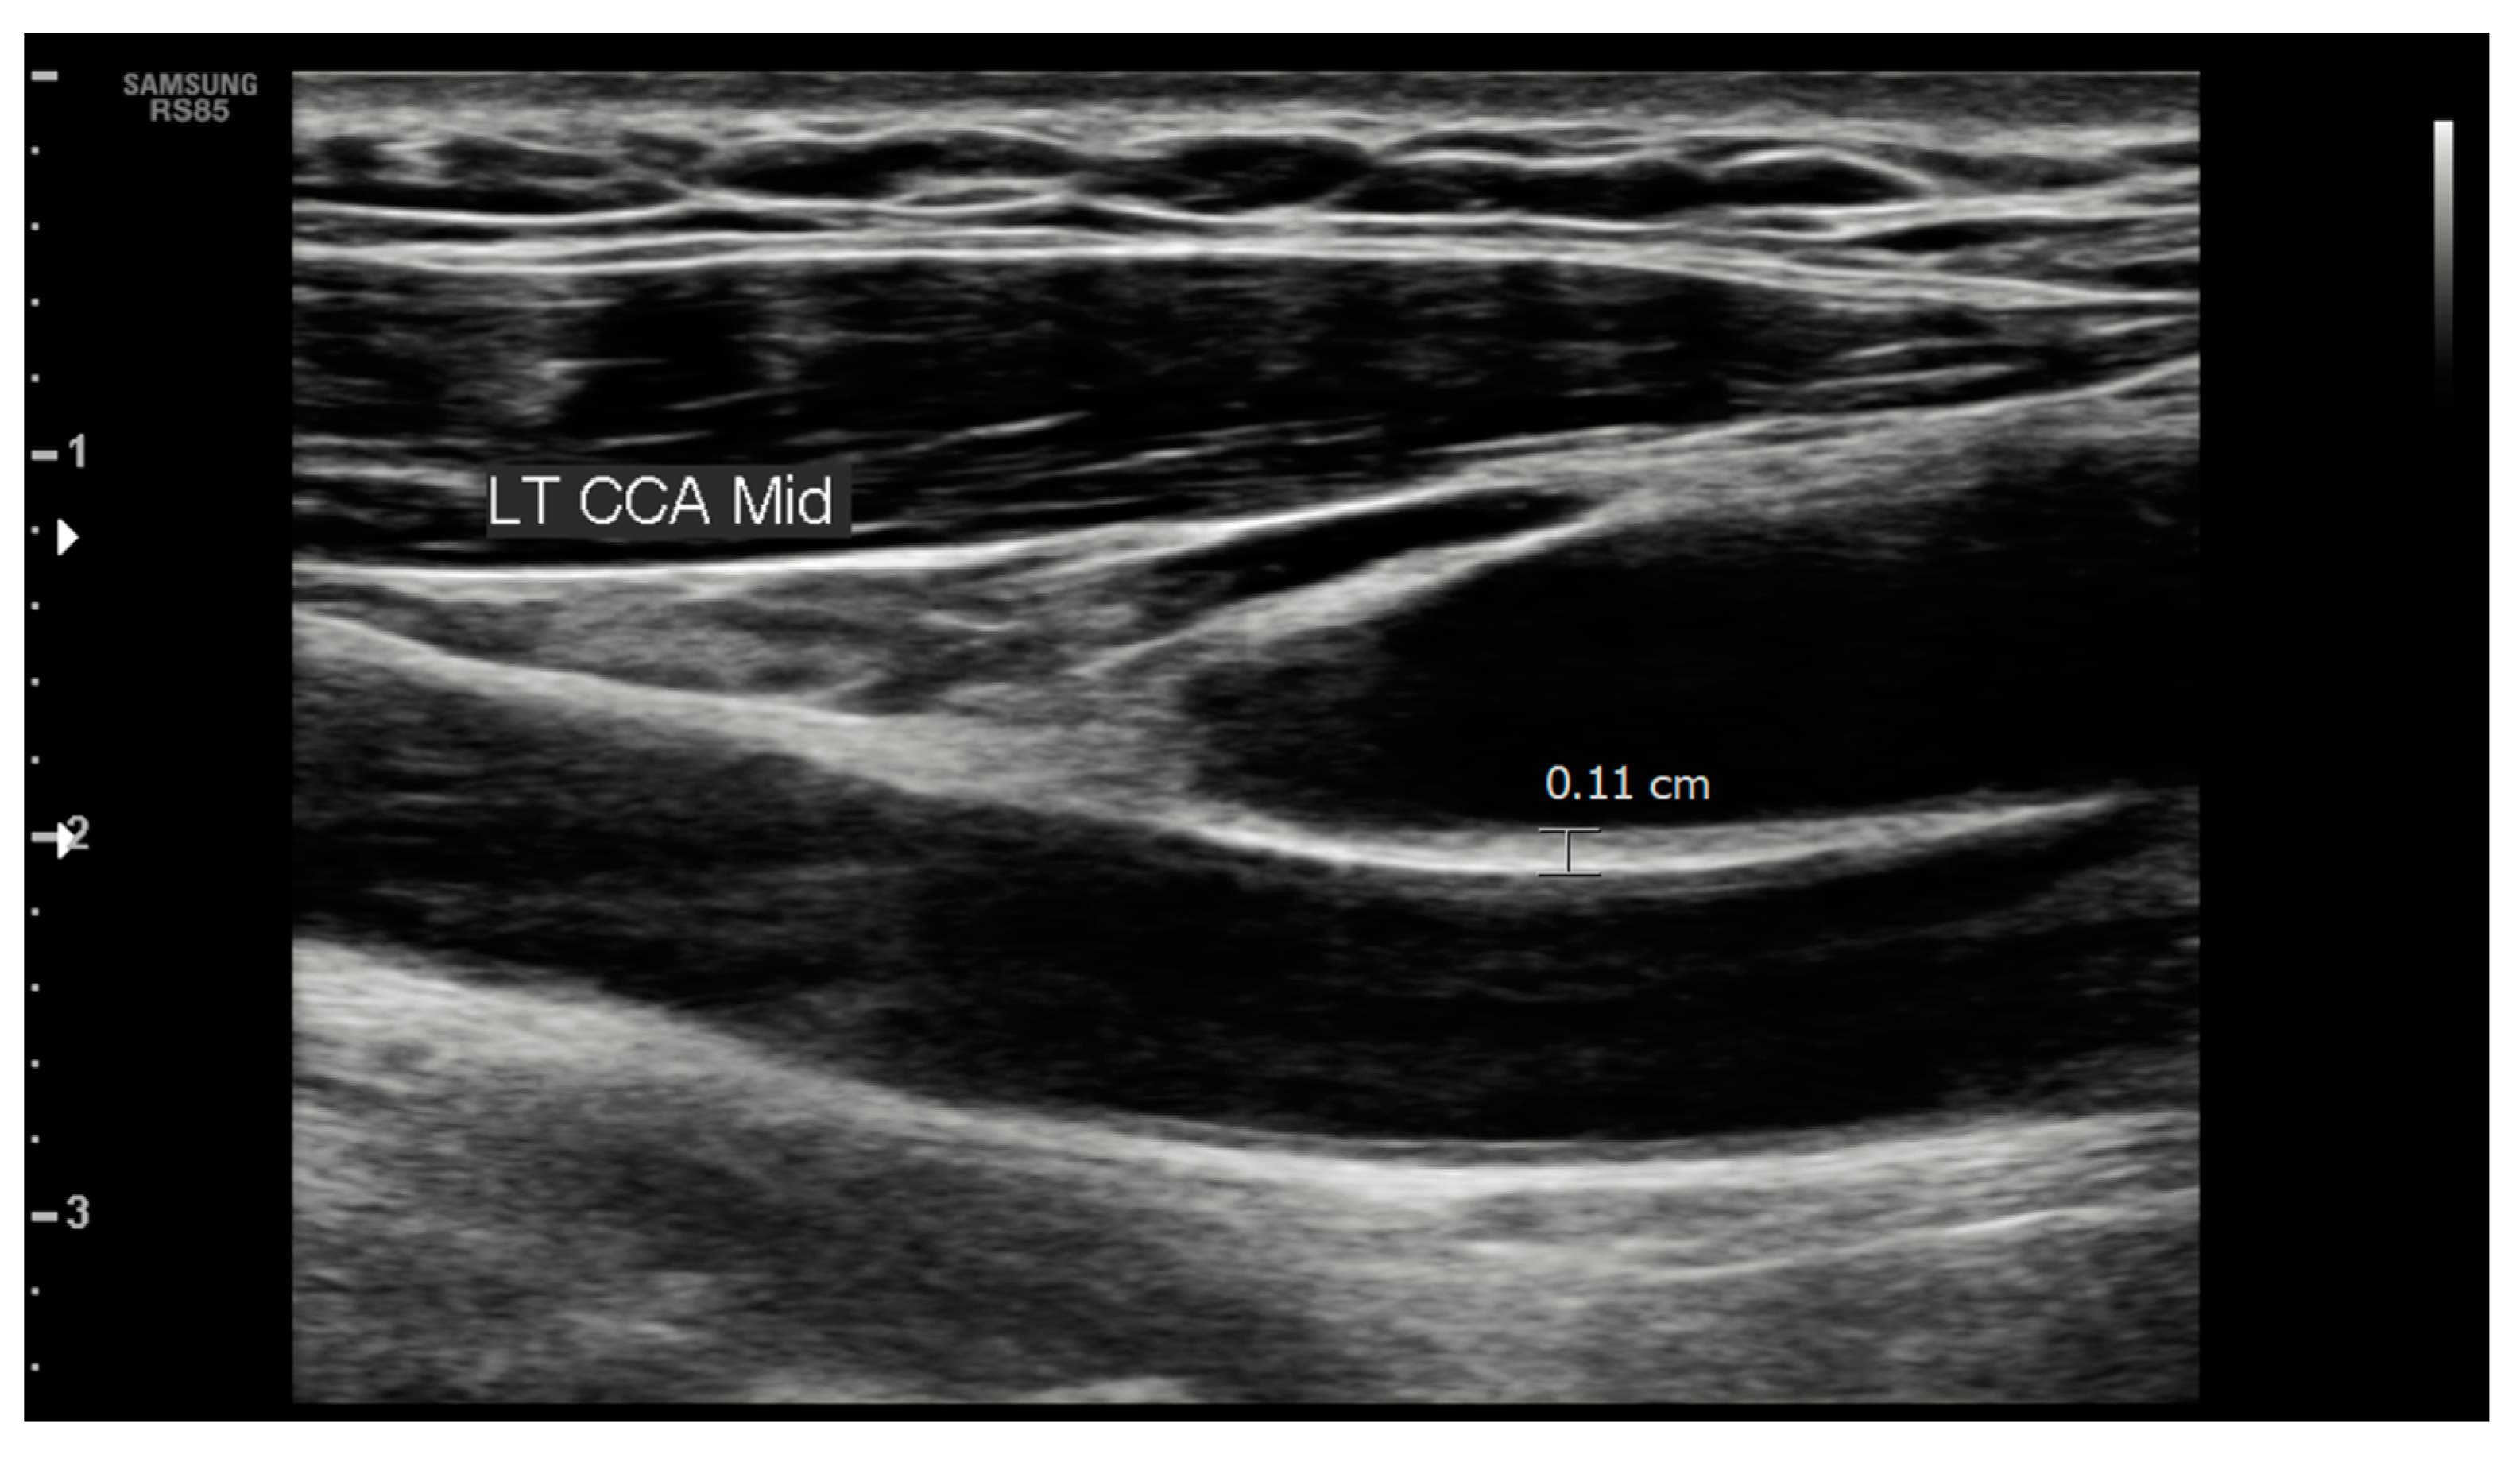

2.3. Carotid and Femoral Ultrasound